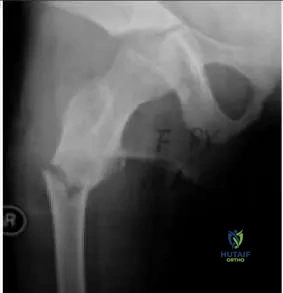

Question 12

The patient presented in the radiograph (Slide) has a slight, painless limp. Which of the following is the most likely diagnosis:

Orthopedic Prometric Exam Chapter 3 Image

Explanation

This patient has multiple â ground-glassâ lesions and one cystic lesion, as well as bowing in the subtrochanteric region. The patient was diagnosed with fibrous dysplasia.